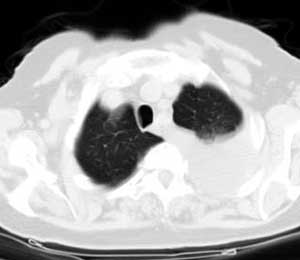

标题: CT0563:病历讨论,胸膜间皮瘤?

测ct值3-6hu,

既然ct值是3-6hu,还不如考虑包裹性积液。

请上传纵隔窗。目前还是支技包裹性积液(明显梭形),即使是间皮瘤并积液也少梭形的。

从图片看,包裹性积液好象更合理,梭形,ct值3-5hu(在哪看到的?);胸膜间皮瘤如此规则,不多见。

左侧背部胸膜肥厚,伴包裹性积液,不考虑间皮瘤.

同意以上各位的高见,首先考虑包裹性积液,1.胸膜间皮瘤积液量一般较大,以游离性积液更为常见,2.可以看到增厚的胸膜结节